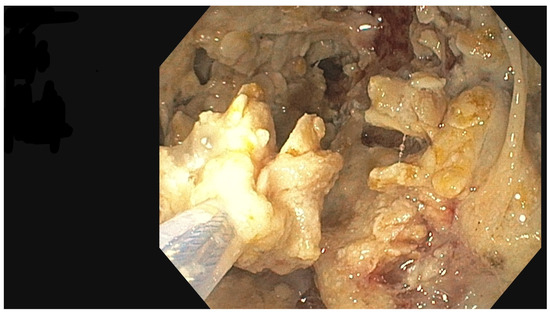

The PEN procedure was performed under general anesthesia with endotracheal intubation in the supine position. Percutaneous endoscopic necrosectomy was performed under the guidance of ultrasound (using a Logiq P9, convex C1-6 MHz probe) and fluoroscopy. Following the establishment of percutaneous drainage, Cook Medical Acrobat 2 AWG2-35-45 guidewire was inserted and looped inside the lumen of the necrotic collection (Figure 1 and Figure 2) to be followed by implantation of a fully coated self-expandable Evolution® esophageal controlled-release stent 120 mm or 150 mm in length and 20 mm in diameter (Figure 3 and Figure 4). A flexible Evis Exera III CF-H190L endoscope–gastroscope (Olympus) was then inserted into the necrotic collection through the lumen of the esophageal stent, and a percutaneous endoscopic necrosectomy procedure involving mechanical removal of necrotic tissue from the collection under direct endoscopic image guidance was performed (Figure 5, Figure 6 and Figure 7). A Dormia basket (Figure 8) was used to remove necrotic tissue. In the course of the percutaneous endoscopic necrosectomy procedure, the necrotic collection was extensively flushed with physiological saline, and the contents from the reservoir were aspirated. The PEN procedure was considered complete upon removal of demarcated necrotic tissues or upon bleeding from the inflammatory granulation tissue within the necrotic collection. If subsequent percutaneous endoscopic necrosectomy procedures were required in the same patient, the esophageal stent was left in the percutaneous position, and one or two 16 Fr silicone drains (depending on the size of the collection) were inserted into the lumen of the necrotic collection through the stent to maintain patency. The drain(s) were used to flush the collection with 100 mL of physiological saline 6 times a day. Following the completion of endoscopic treatment using percutaneous access, the esophageal stent was removed, and the stenting site was secured with a stoma bag to drain the remaining contents from the residual necrotic collection (Figure 9).

Figure 5. Percutaneous endoscopic necrosectomy procedure. Source: Department of General, Gastroenterological, and Oncological Surgery, L. Rydygier Regional Hospital in Toruń.

Figure 6. Walled-off pancreatic necrosis collection. Source: Department of General, Gastroenterological, and Oncological Surgery, L. Rydygier Regional Hospital in Toruń.